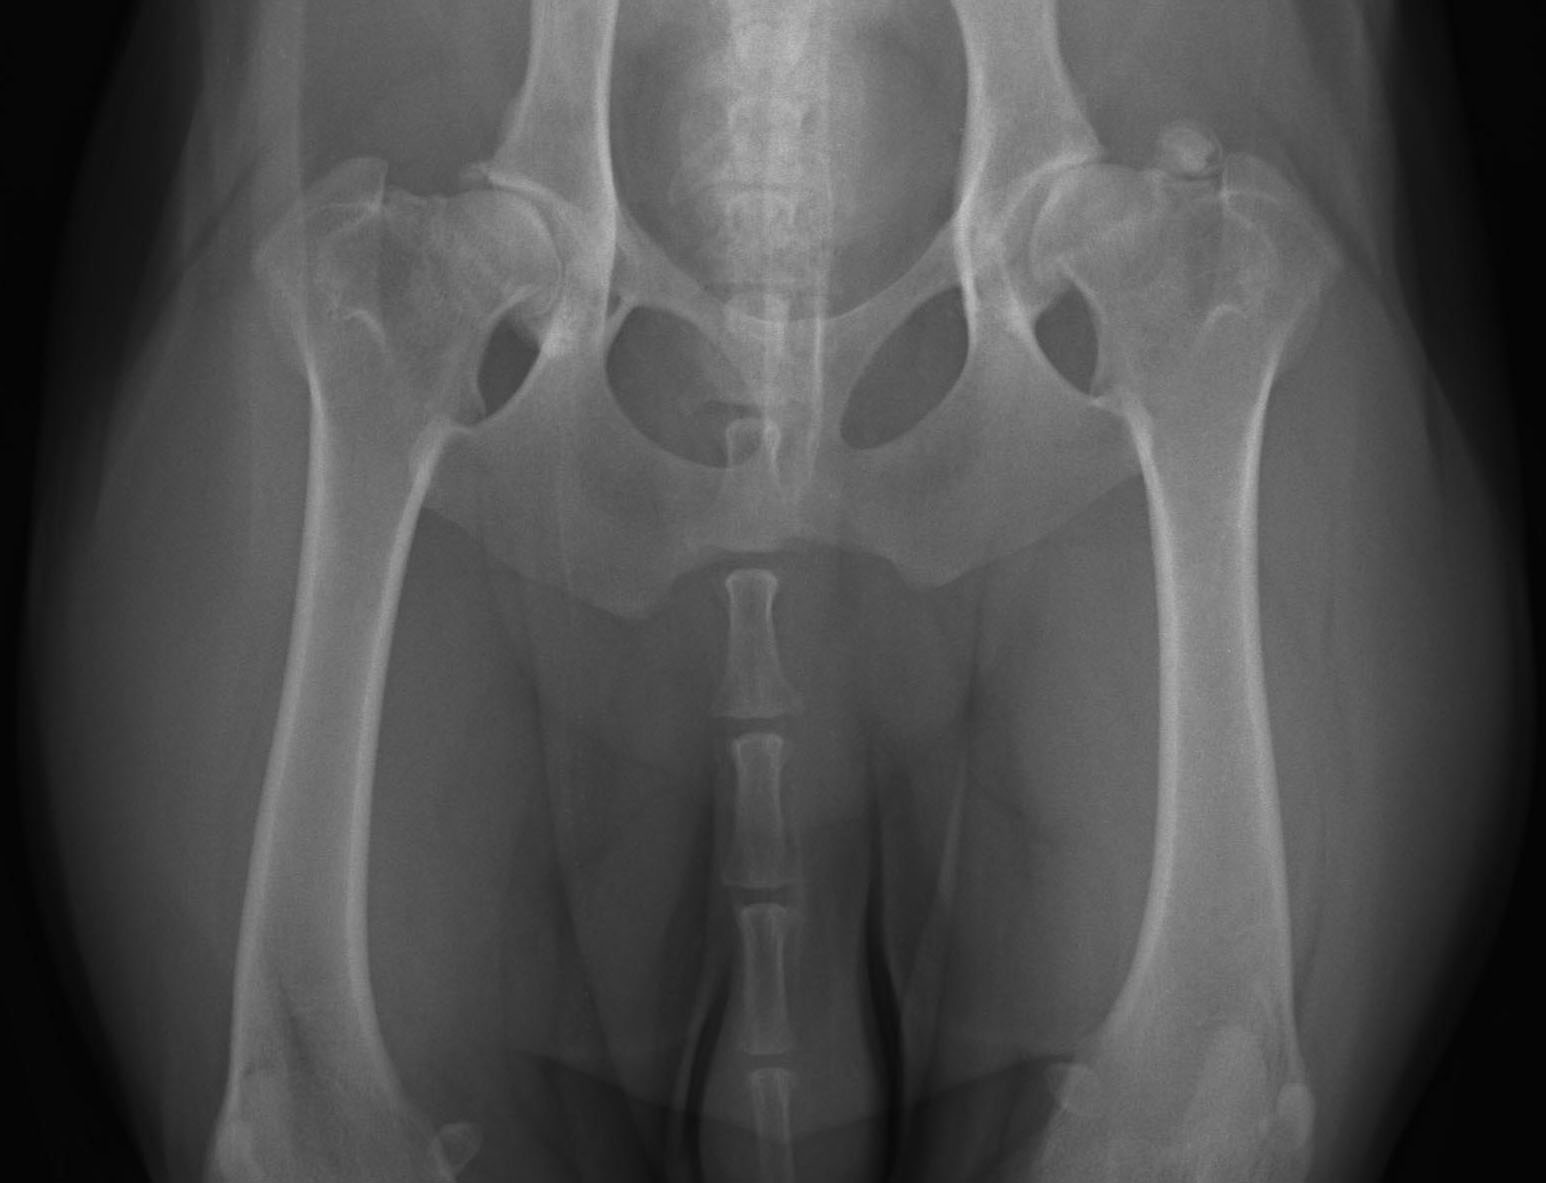

Heupdysplasie (HD)

Heupdysplasie (HD) is een ontwikkelingsstoornis van de heupgewrichten. Het kan erfelijk zijn, maar omgevingsfactoren spelen ook een rol bij de ontwikkeling. Een hond kan veel last hebben van HD, maar dat hoeft niet. Aan de buitenkant kun je niet zien of een hond HD heeft, dus als je hond goed kan lopen, hoeft dat nog niet te zeggen dat zijn heupen perfect zijn. Om echt te kunnen zien of je hond HD heeft, zijn (digitale) röntgenfoto’s van zijn heupen nodig.